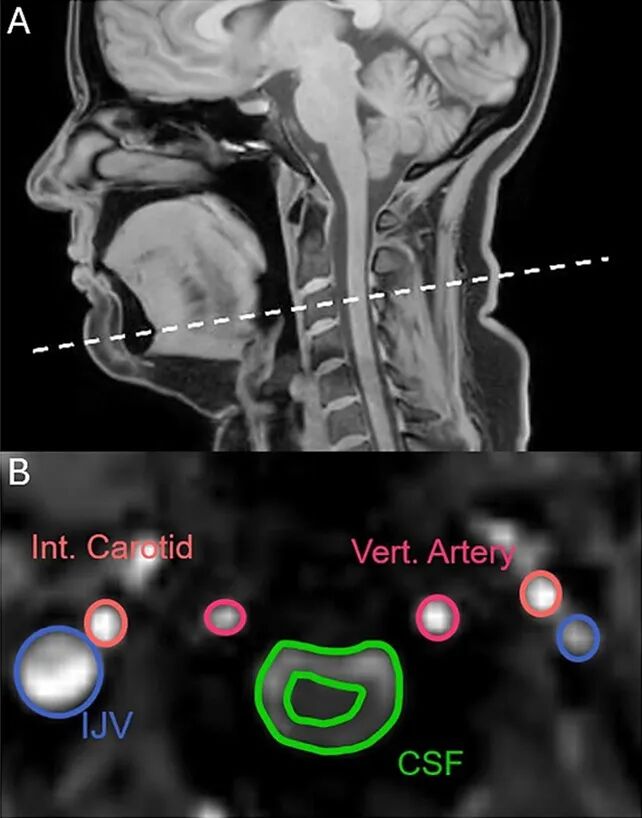

脑脊液(Cerebrospinal Fluid,简称 CSF),顾名思义,就是存在于我们大脑和脊髓周围的液体,可以在大脑和脊髓之间循环流动。它包裹在我们大脑周围,能对大脑起到缓冲作用。不过它也有其他作用,比如维持离子浓度,让大脑的神经细胞能正常运作。还有研究则指出,脑脊液就像是“清洁工”,能把脑细胞周围的代谢废物带走。

在近期的一项研究中,科学家招募了22名健康的成年人,让他们接受了MRI扫描,在扫描时,这些参与者会正常呼吸、(被传染)打哈欠、抑制打哈欠或者是深呼吸。

结果出乎研究人员的意料。深呼吸和打哈欠时,脑脊液的流动都会变强,但是它们流动的方向则截然相反。研究者原本以为,打哈欠就像是“用力深呼吸”,但并非如此:打哈欠时,脑脊液会往脊髓的方向流动。与此同时,颈部的静脉血也会向下走。

科学家从脑脊液的流向发现,打哈欠并不是深呼吸的一种,而是另外一种“特殊能力”。|参考资料1

这种流动方向和深呼吸完全相反,这说明,打哈欠的确是一种十分特殊的能力,也可能有着特殊的作用。